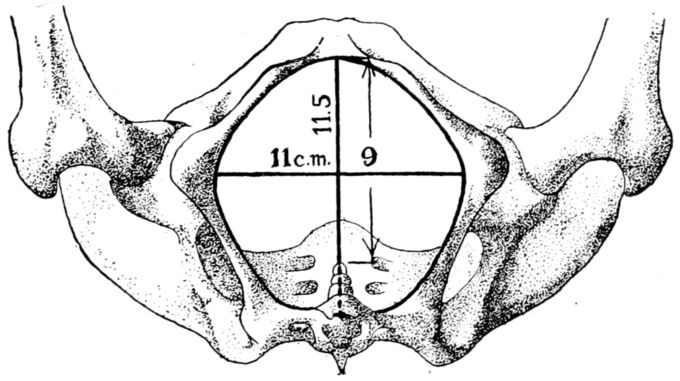

22The pelvic cavity as a whole is divided into the true and false pelves by a constriction of the entire structure known as the brim or inlet. The inlet is not round, its antero-posterior diameter being shortened by the sacro-vertebral joint which protrudes forward and gives the opening something of a blunt, heart-shaped outline. (Fig. 2.)

Fig. 2.—Diagram of the pelvic inlet, seen from above, with most important diameters.

The inlet has four measurements of obstetrical importance: the antero-posterior, or true conjugate, which is the distance from the top of the symphysis pubis to the prominence of the sacrum, and is normally 11 centimetres; the transverse diameter, which is at right angles to the true conjugate and is the greatest width of the inlet, measuring from a point on one side of the brim to the corresponding point on the other, is normally 13.5 centimetres, and the two diagonal measurements, known respectively 27as the right and left oblique diameters, which are normally 12.75 centimetres.

Although it is very important to the expectant mother that all of these dimensions be of normal length, the length of the true conjugate, or conjugata vera, is of the gravest importance of all because it is the shortest diameter through which the child’s head must pass. If it is shorter than normal, the channel may be too constricted for the full-term baby’s head to pass through comfortably, thus making a spontaneous delivery extremely difficult, or even impossible.